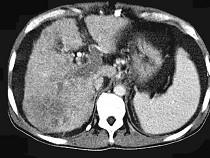

问题 女性,50岁,曾患乙型肝炎,肝硬化多年,右上腹胀痛1月余,CT检查如图所示,最全面的诊断是()

选项 A.肝硬化、腹水伴胆管细胞癌 B.肝硬化、腹水伴原发性肝癌 C.肝硬化、腹水、肝癌并门脉癌栓 D.肝硬化、腹水并肝脓肿 E.肝硬化、腹水并肝血管瘤

答案 C